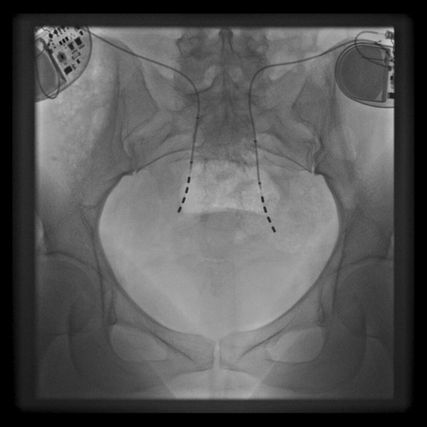

Die Blasenfunktionsstörung muss klinisch, urodynamisch und endoskopisch abgeklärt werden. Ein zweischrittiges Vorgehen wird empfohlen. Erst erfolgt eine Testphase, bei der perkutan und unter Röntgenkontrolle entweder die definitiven Stimulationssonden (sog. «tined leads») oder Testsonden für den sog. PNE-Test (perkutane Neuroevaluation) implantiert werden (Abb. 2). Die Implantation erfolgt in einer modifizierten Bauchlage mit Lokalanästhesie und ggf. Analgosedation oder in Allgemeinanästhesie.

Über einen provisorischen, externen Impulsgeber kann dann eine längerfristige, zum Teil mehrwöchige (bei «tined leads») oder eine kurzfristige, nur wenige Tage (bei PNE) dauernde Testtherapie erfolgen. Wenn sich innerhalb der Testphase die Beschwerden um mindestens 50% verbessern, wird von einem erfolgreichen Test ausgegangen. Danach ist je nach Art der Testung nur noch die subkutane Implantation der Impulsgeber oder aber eine komplette Implantation von Sonde und Impulsgeber nötig (Abb. 3). Die Implantation kann unilateral oder bilateral erfolgen, meist werden die Sonden an die sakrale Nervenwurzel S3 gelegt.